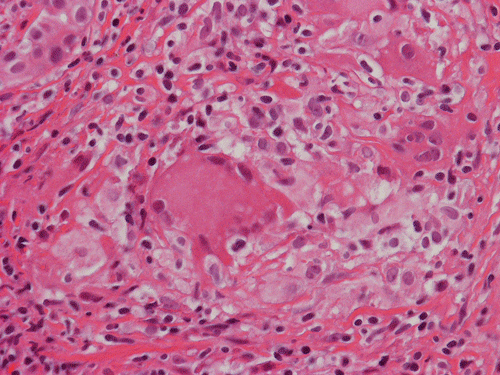

Pathology of the Case: At low magnification, a few small nodules (arrow in Panel A) can be seen with the hematoxylin and eosin stained section. On medium magnification, these nodules correspond to sharply defined granuloma without necrosis. These granuloma are not associated with a high density of lymphocytes in the surrounding liver parenchyma (Panel B and C). Multinucleated giant cells (arrow in Panel C, magnified in Panel D). On reticulin stain, there are reticulin fibers that extends into the granuloma (Panel E). Trichrome stain demonstrated bridging fibrosis (Panel F). The granuloma are well defined and some of them are surrounded by fibrous tissue (Panel G). Immunohistochemistry demonstrated preservation of bile ductules as well as proliferation of ductules (Panle H). No residual ductules are noted in the granuloma as revealed by immunohistochemistry for CK7 (Panel I). Neither acid fast bacilli or fungal organisms are identified by acid fast stain and Gomori's methenamine silver (GMS) stain.

Histopathologic features of sarcoidosis include scattered granulomas in the liver, which may tend to be portal or periportal. Multinucleated giant cells, epithelioid cells, and a variable but usually minimal inflammatory cellular response is present. The granulomas, like in sarcoidosis occuring in other organ systems, tend to be well-demarcated or "clear cut", several granulomas are often comparable in size, and necrosis is not typically present. Asteroid bodies, intracellular vacuolated structures resembling a sea anemone, may be found within the giant cells. Large basophilic, round to roughly oval, and concentrically laminated, Schaumann bodies may be evident in the sarcoid granuloma. None of these inclusions are pathognomonic feature of sarcoidosis, however, do suggest this diagnosis. Ductopenia, cholestasis and features of chronic cholestasis resembling PBC have been described in the cases of sarcoidosis. Severe fibrosis and cirrhosis in conjunction with portal hypertension may be present in sarcoidosis. End stage liver disease in sarcoidosis has been successfully treated by orthotopic liver transplant and recurrent disease has been reported in one such case. Reticulin fibers has a tendency to extend into the granulomas as illustrated in this case.